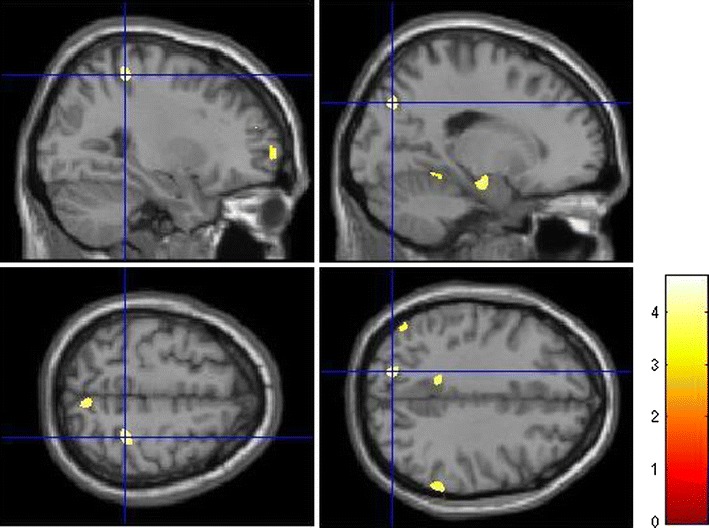

In addition, we found significant effects on a FDR-corrected level contralateral in the right hippocampus (Fig. 1) as well as in anterior prefrontal (Fig. 2) and intraparietal cortices (Fig. 3), in cortical regions of the temporal lobe and bilaterally in the cerebellum.

Fig. 2.

Effects of DTNBP1 SNP rs2619522 on grey matter volumes of anterior prefrontal cortex. Carriers of the G allele (risk allele) exhibit significantly higher grey matter volumes in these brain areas than T/T homozygotes. p < 0.001 (uncorrected); extent threshold = 100 voxels

Fig. 3.

Effects of DTNBP1 SNP rs2619522 on grey matter volumes of parietal cortices. G allele-carriers (risk allele) exhibit significantly higher grey matter volumes in these cortical regions than T/T homozygotes. p < 0.001 (uncorrected); extent threshold = 100 voxels